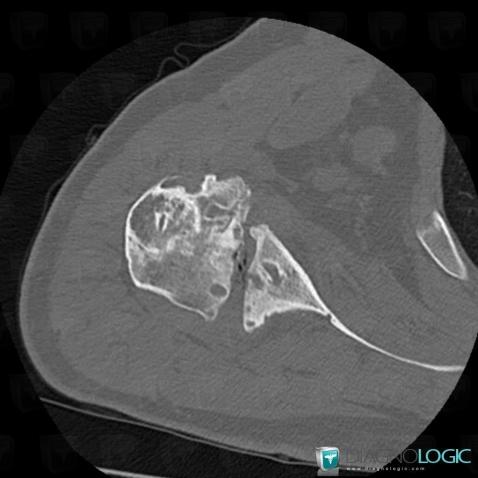

Degenerative joint disease, Scapula, CT

Here is the specific information in the key image above:

- Diagnosis Degenerative joint disease, Location(s) Scapula, with gamuts Epiphyseal osteolysis